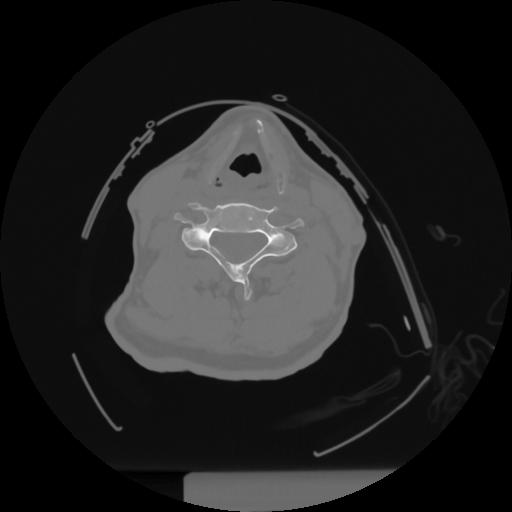

12 P.BLANDAS,,Vol,0.5,P.BLANDAS,,